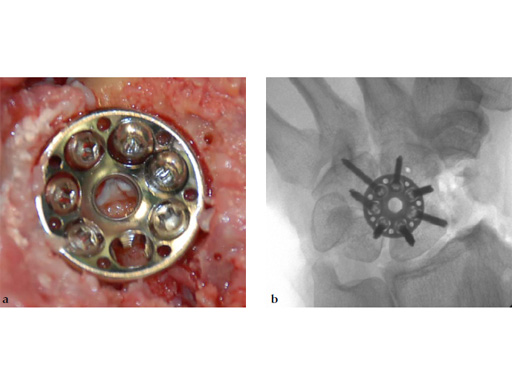

Fig 6ab Final appearance of fixed plate.